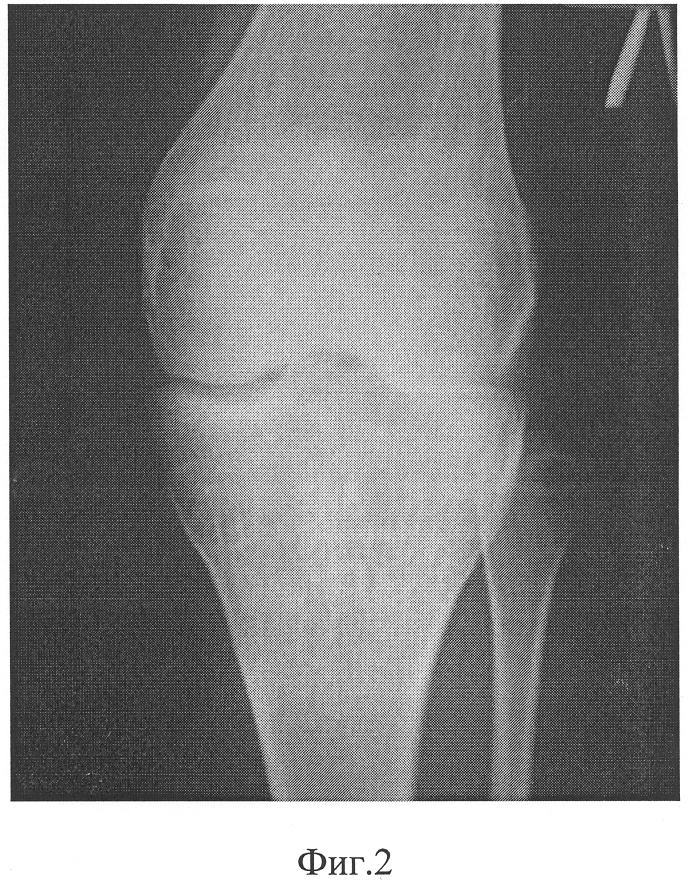

Фиг.4 – после операции и наложения аппарата внешней фиксации;

В СарНИИТО 13.12.05 было проведено оперативное вмешательство по запланированной схеме (фиг.5). Произвели дугообразный разрез по передневнутренней поверхности проксимального отдела левой голени длиной 12 см. В верхней трети левой большеберцовой кости выполнена корригирующая многоплоскостная остеотомия с формированием внесуставно костно-хрящевого суставного фрагмента. На задней поверхности голени вырезали клин углом в 10° и шириной 8 мм. Затем была пересечена в средней трети малоберцовая кость. Проведенными в сагиттальной плоскости П-образно изогнутой спицей Киршнера и стержнем костно-хрящевой фрагмент зафиксирован в аксиальной плоскости. Интраоперационно под рентгеноконтролем на голень наложен двухсекционный спице-стержневой аппарат внешней фиксации (фиг.4). Спица и стержень закреплены на верхней базовой опоре аппарата посредством тяговых устройств.

Со второго дня после операции была начата дистракция костно-хрящевого фрагмента в поперечном направлении со скоростью 0,03 мм за 1,5 часа. Расчетный срок дистракции составил 32 дня.